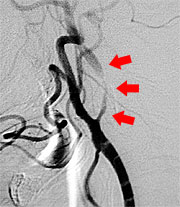

さて当科では脳梗塞予防手術を積極的に行っています。最近食生活の欧米化で内頚動脈起始部狭窄症が増加しています。この病気に対しては外科的治療と血管内治療がありますが、当科では主に外科的治療によって内頚動脈の厚くなった内膜を剥離して血管を広げ、脳梗塞を予防しています(図9、10)。